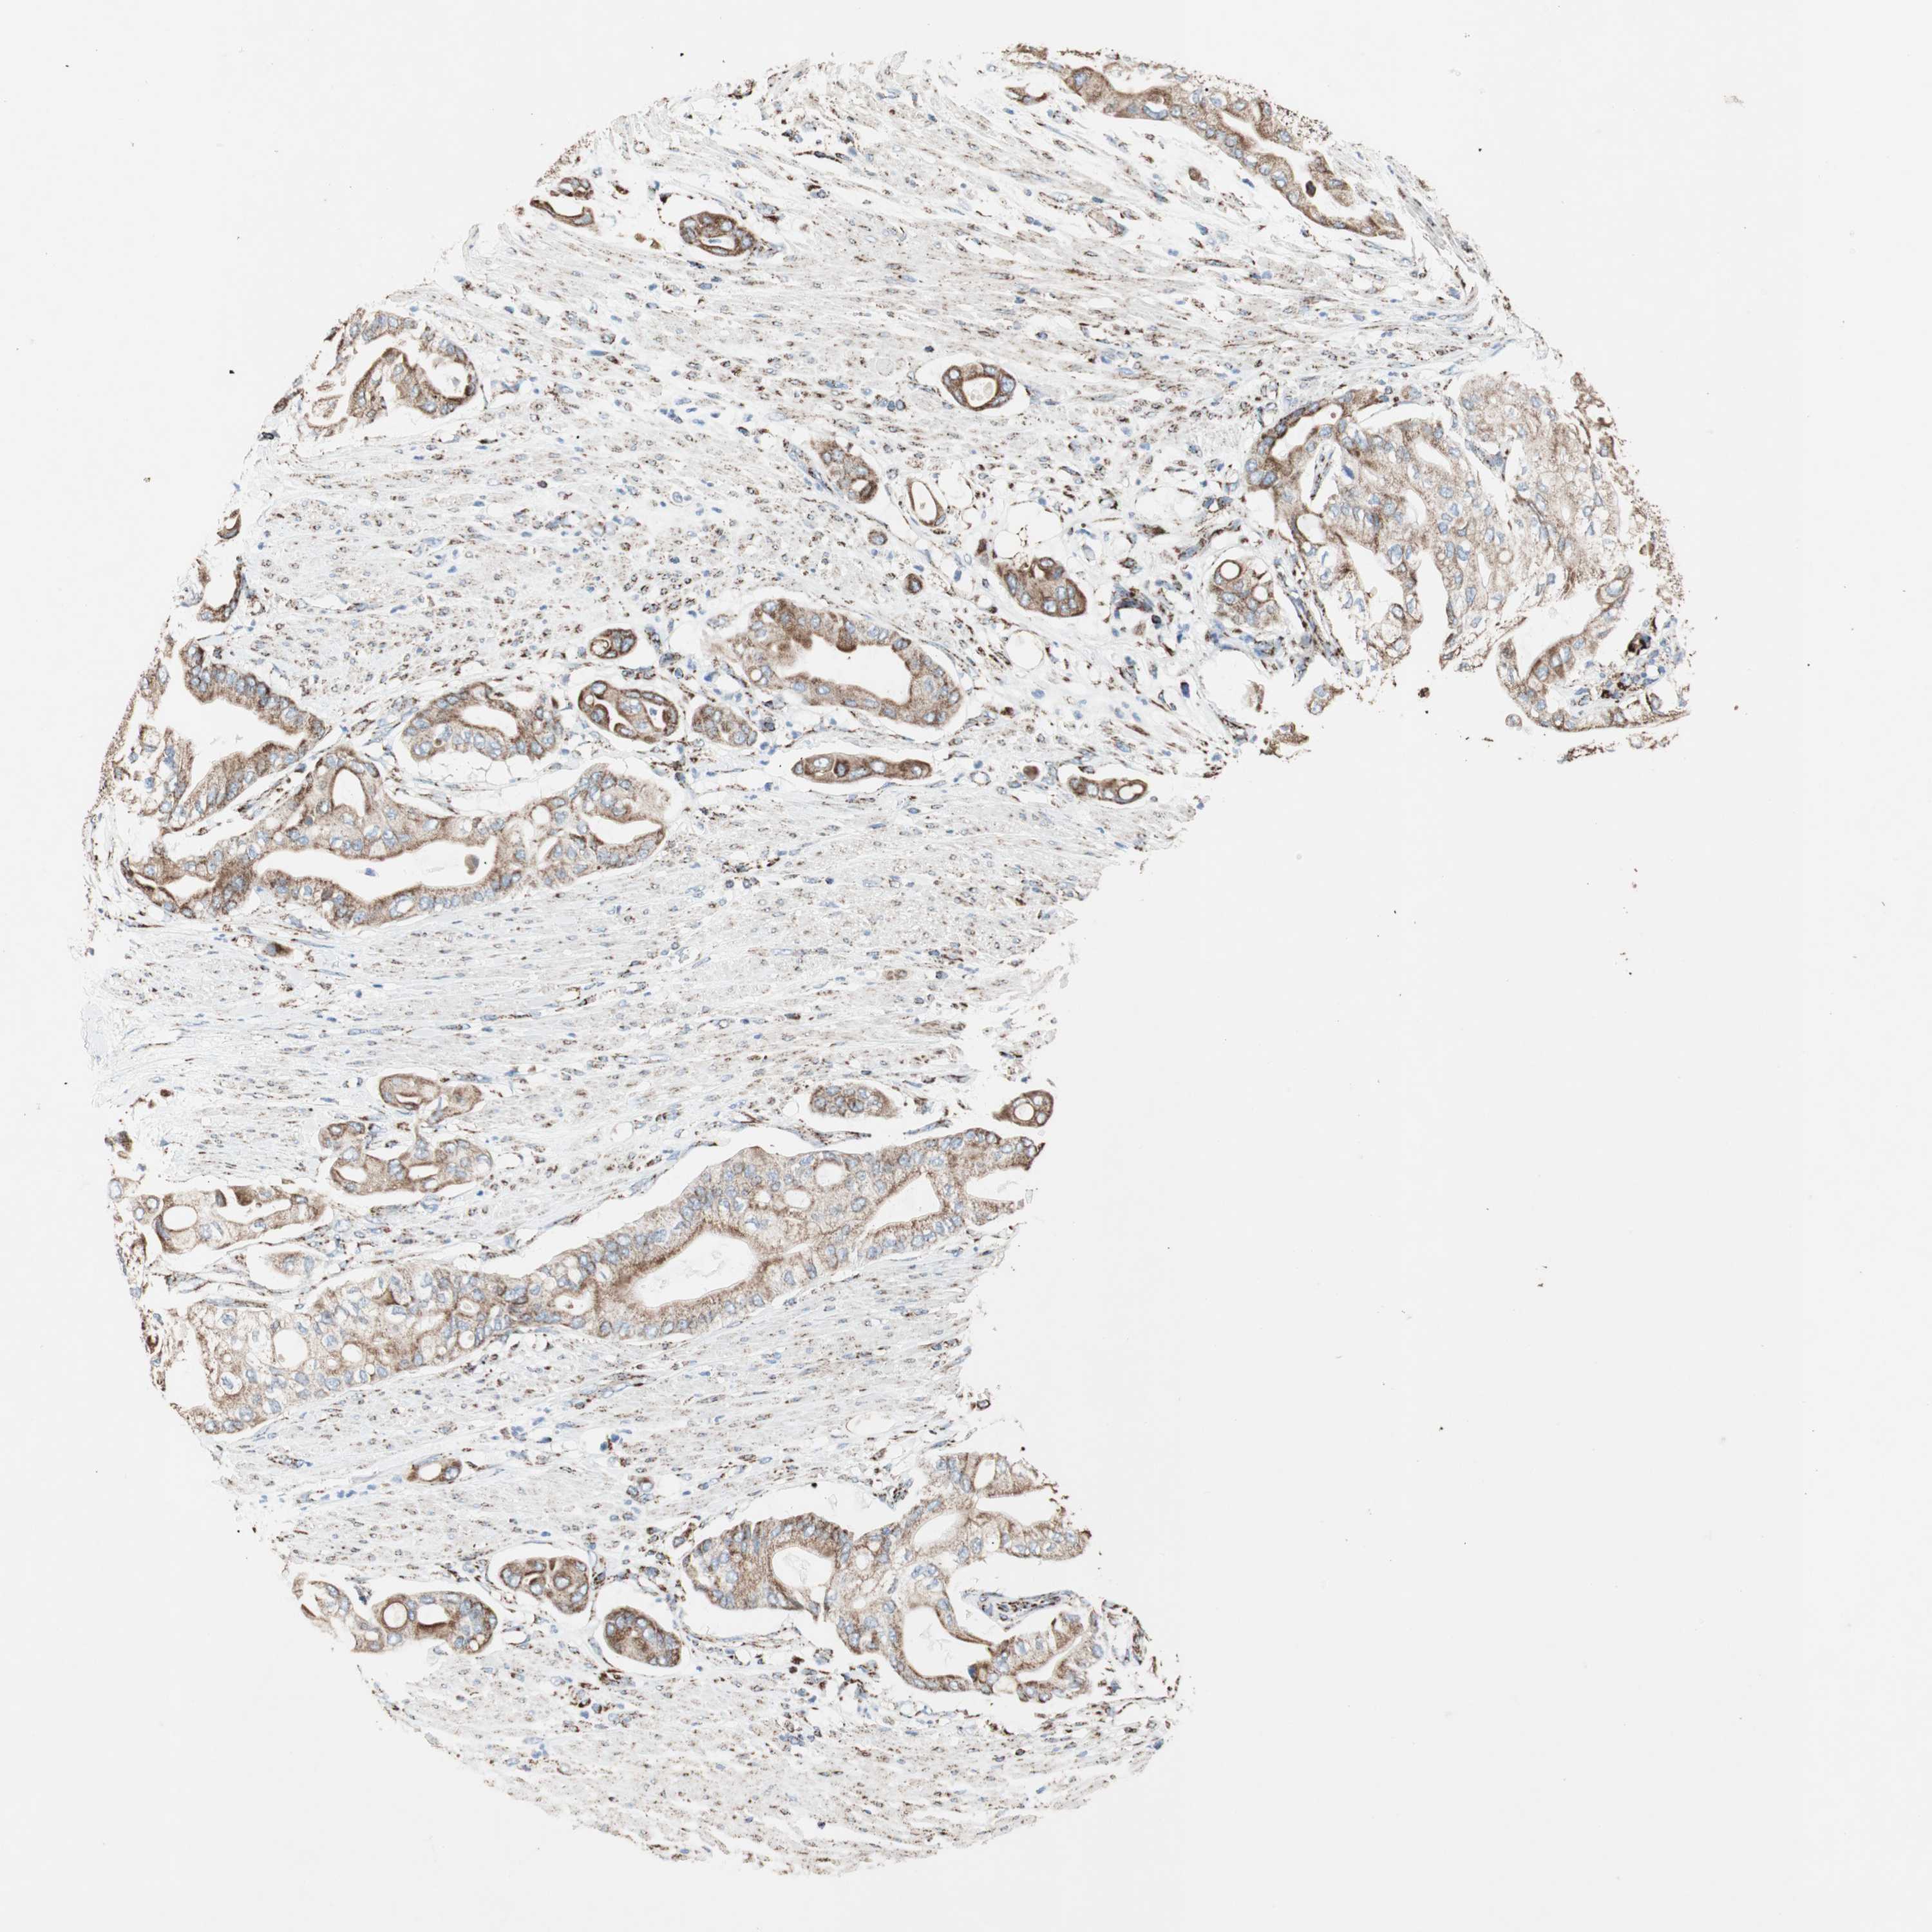

PANCREATIC CANCER - Protein expressioni

A mouse-over function shows sample information and annotation data. Click on an image to view it in a full screen mode. Samples can be filtered based on level of antibody staining by selecting one or several of the following categories: high, medium, low and not detected. The assay and annotation is described here.

Note that samples used for immunohistochemistry by the Human Protein Atlas do not correspond to samples in the TCGA dataset.

Antibody stainingi

Antibody staining in the annotated cell types in the current human tissue is reported as not detected, low, medium, or high, based on conventional immunohistochemistry profiling in selected tissues. This score is based on the combination of the staining intensity and fraction of stained cells.

Each image is clickable and will lead to virtual microscopy that enables deeper exploration of all samples and also displays staining intensity scores, fraction scores and subcellular localization as well as patient and tissue information for each sample.

Antibody HPA005572

Staining

High

Medium

Low

Not detected

Intensity

Strong

Moderate

Weak

Negative

Quantity

>75%

75%-25%

<25%

None

Location

Nuclear

Cytoplasmic/membranous

Cytoplasmic/membranous,nuclear

Adenocarcinoma, NOS

Adenocarcinoma, metastatic, NOS